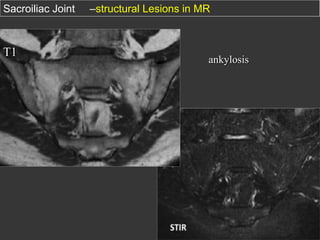

Sacroiliac Joint

T1

–structural Lesions in MR

ankylosis